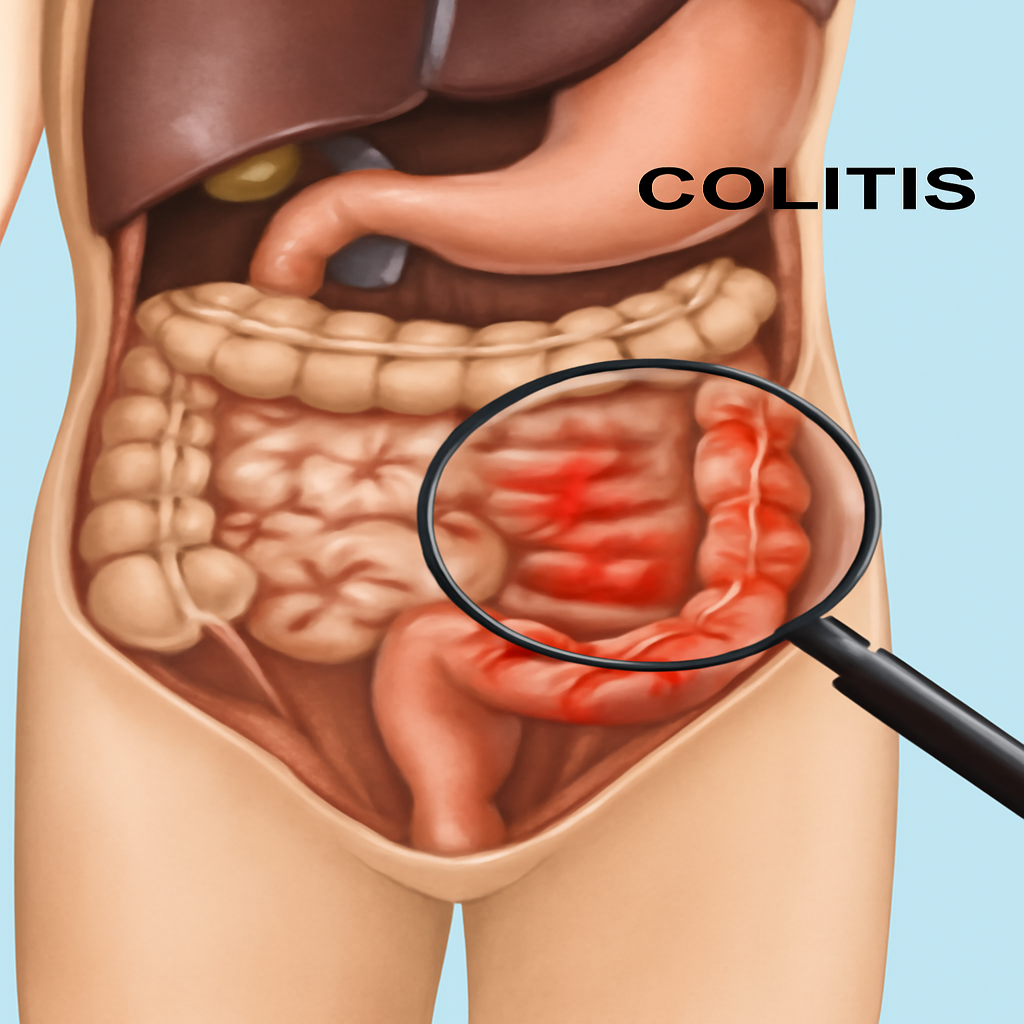

# Anal and Digestive